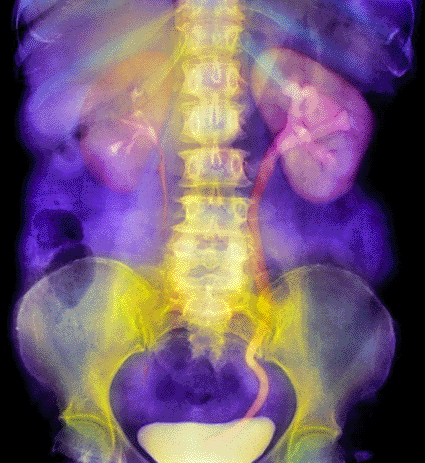

Image: Colored urogram of a patient’s abdomen showing a blocked ureter due to a kidney stone (Photo courtesy of SPL).

Ultrasound Probes Successful in Breaking Up Kidney Stones

A comparatively new ultrasound probe procedure has the highest success rate for breaking down kidney stones in the lower "funnel” region of the kidney, instead of the shock wave treatment used for many years, More...